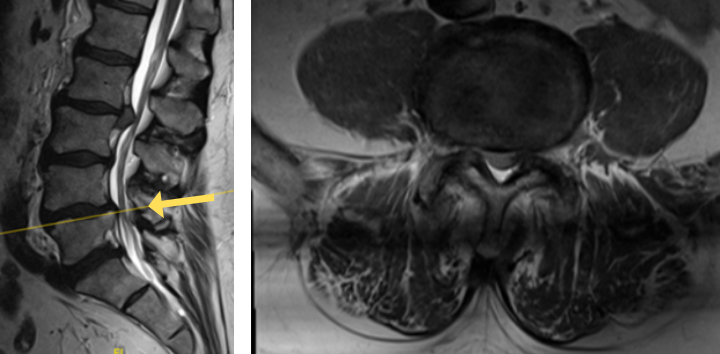

His MRI lumbar spine showed a herniated disc at L2/L3 and a grade 1 spondylolisthesis at L4/L5. Both of these findings were contributing to the patients back and leg pain.

Image 1A shows central stenosis at L4/L5 level associated with grade 1 spondylolisthesis.

Image 1B shows disc herniation at L2/L3.